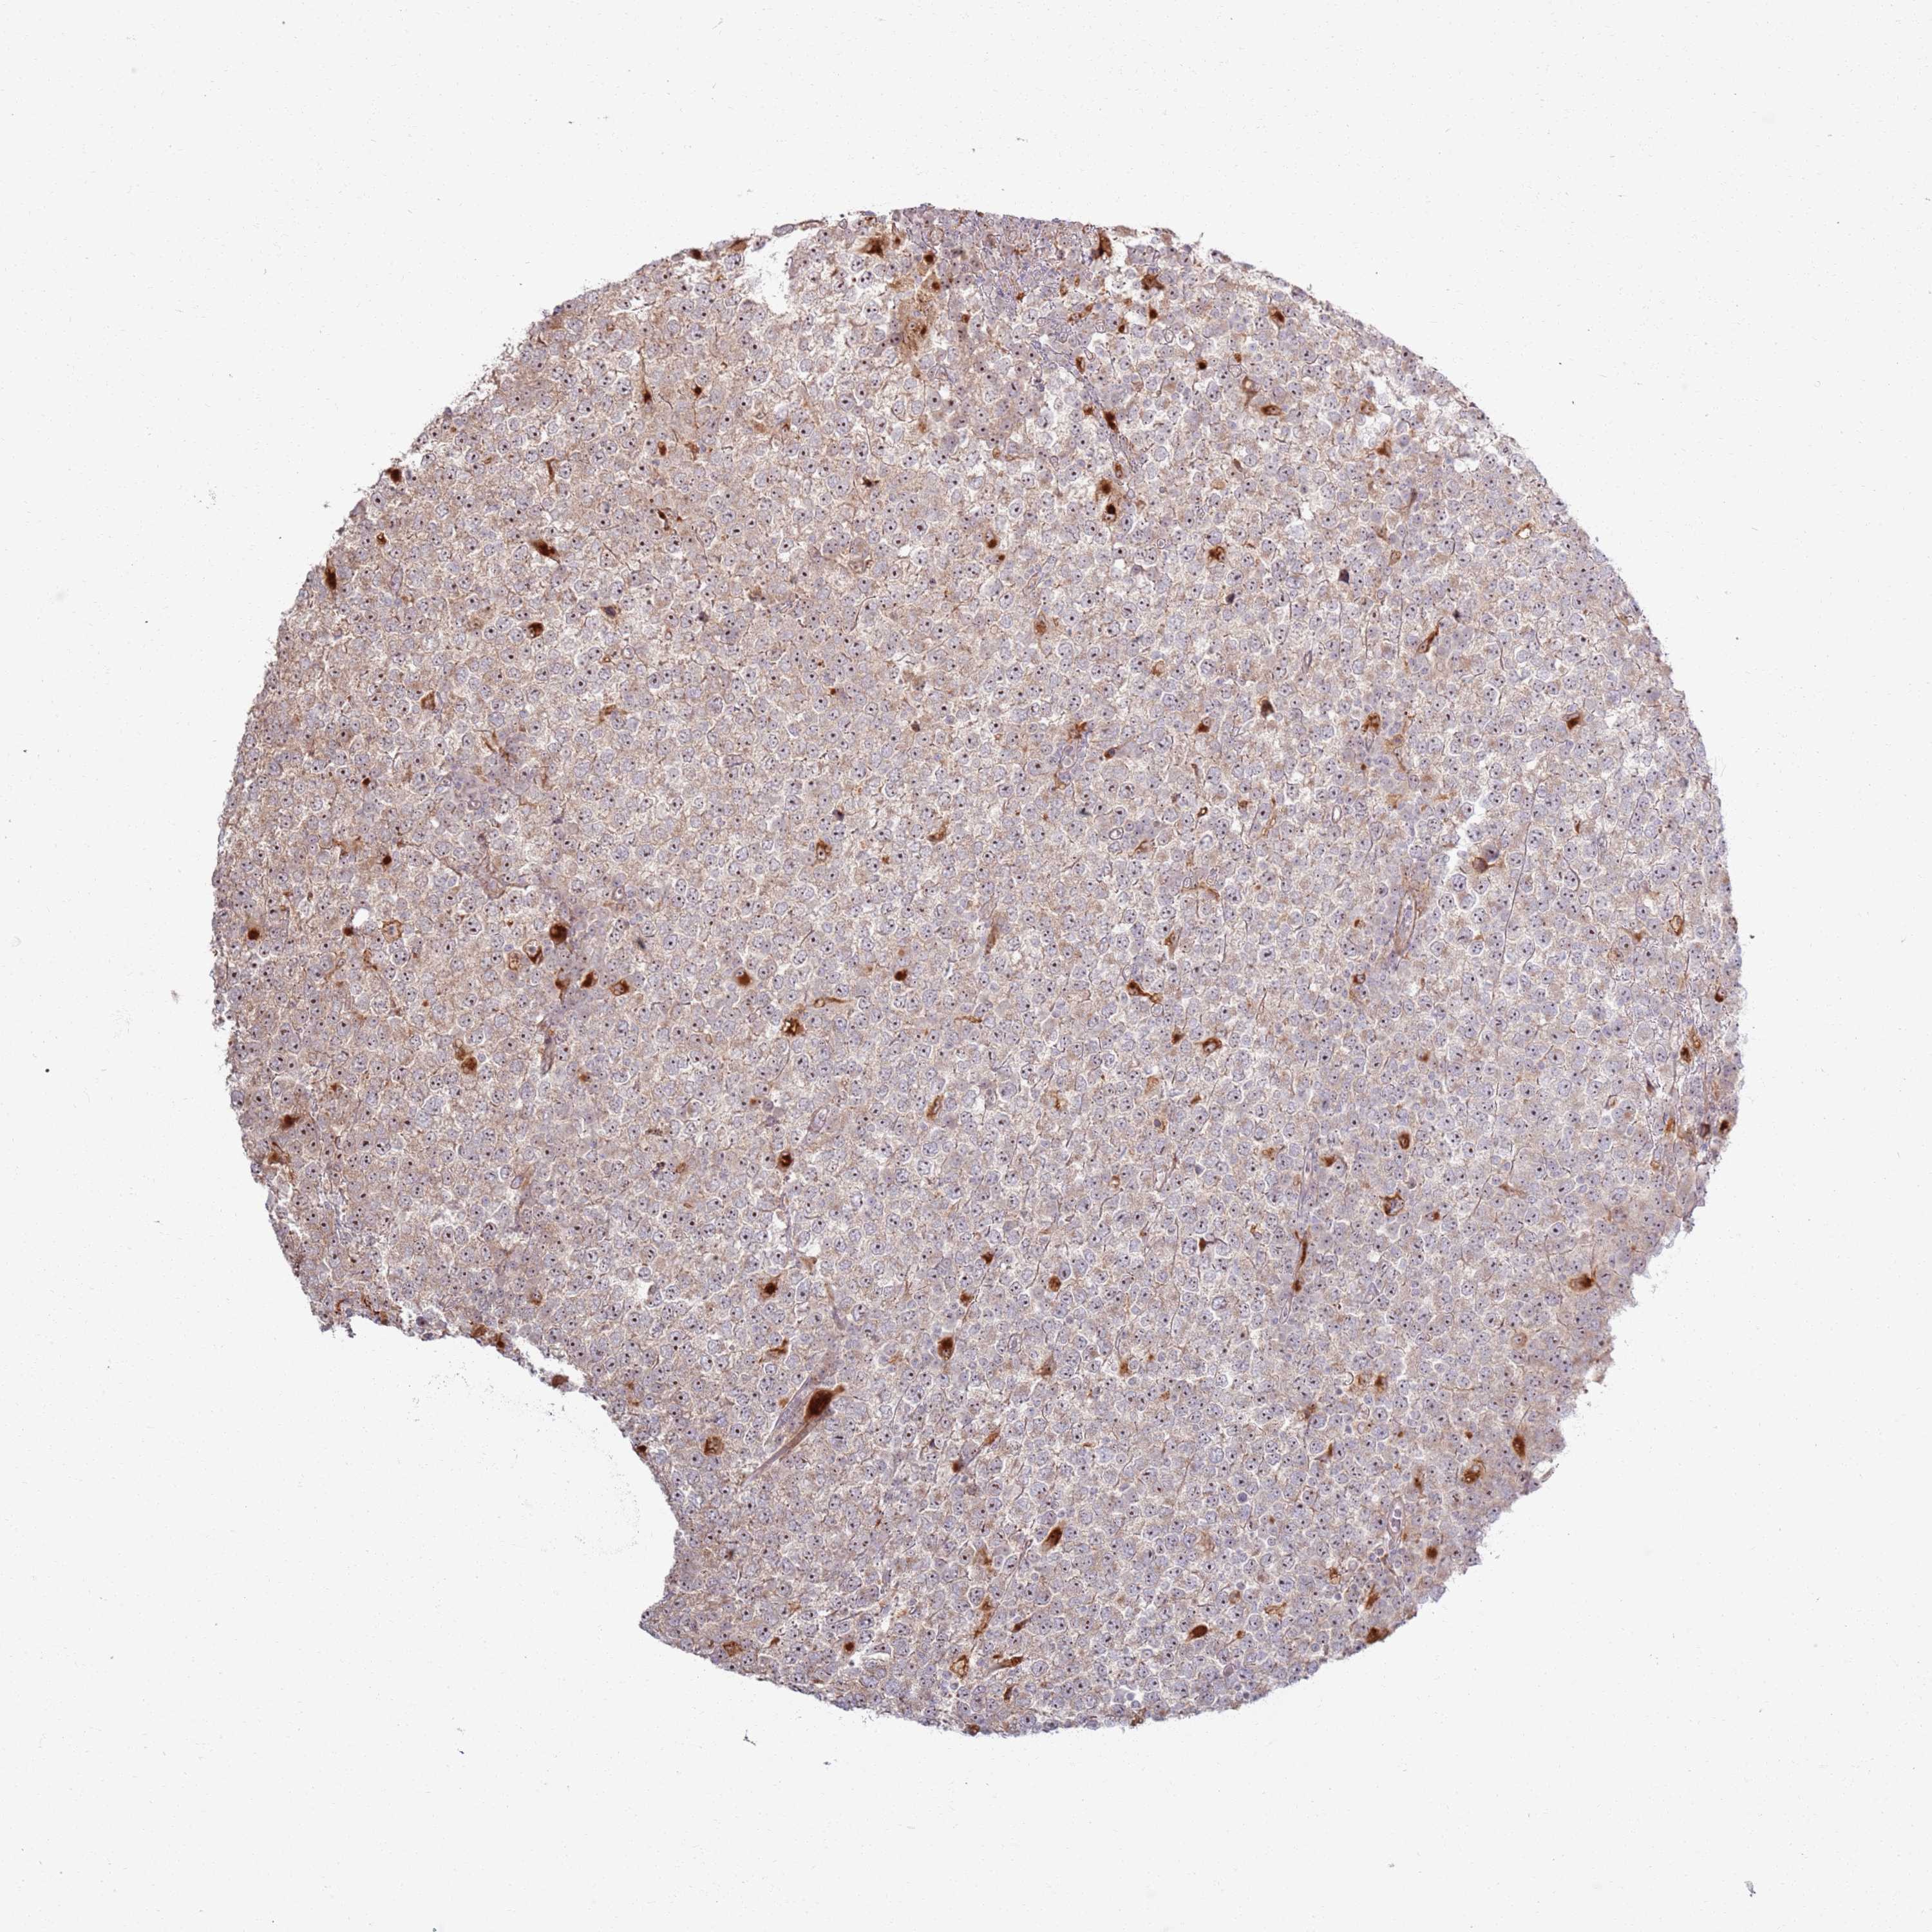

TESTIS CANCER - Protein expressioni

A mouse-over function shows sample information and annotation data. Click on an image to view it in a full screen mode. Samples can be filtered based on level of antibody staining by selecting one or several of the following categories: high, medium, low and not detected. The assay and annotation is described here.

Note that samples used for immunohistochemistry by the Human Protein Atlas do not correspond to samples in the TCGA dataset.

Antibody stainingi

Antibody staining in the annotated cell types in the current human tissue is reported as not detected, low, medium, or high, based on conventional immunohistochemistry profiling in selected tissues. This score is based on the combination of the staining intensity and fraction of stained cells.

Each image is clickable and will lead to virtual microscopy that enables deeper exploration of all samples and also displays staining intensity scores, fraction scores and subcellular localization as well as patient and tissue information for each sample.

Antibody HPA047400

Staining

High

Medium

Low

Not detected

Intensity

Strong

Moderate

Weak

Negative

Quantity

>75%

75%-25%

<25%

None

Location

Nuclear

Cytoplasmic/membranous

Cytoplasmic/membranous,nuclear

Carcinoma, Embryonal, NOS

Seminoma, NOS

Urothelial carcinoma, High grade